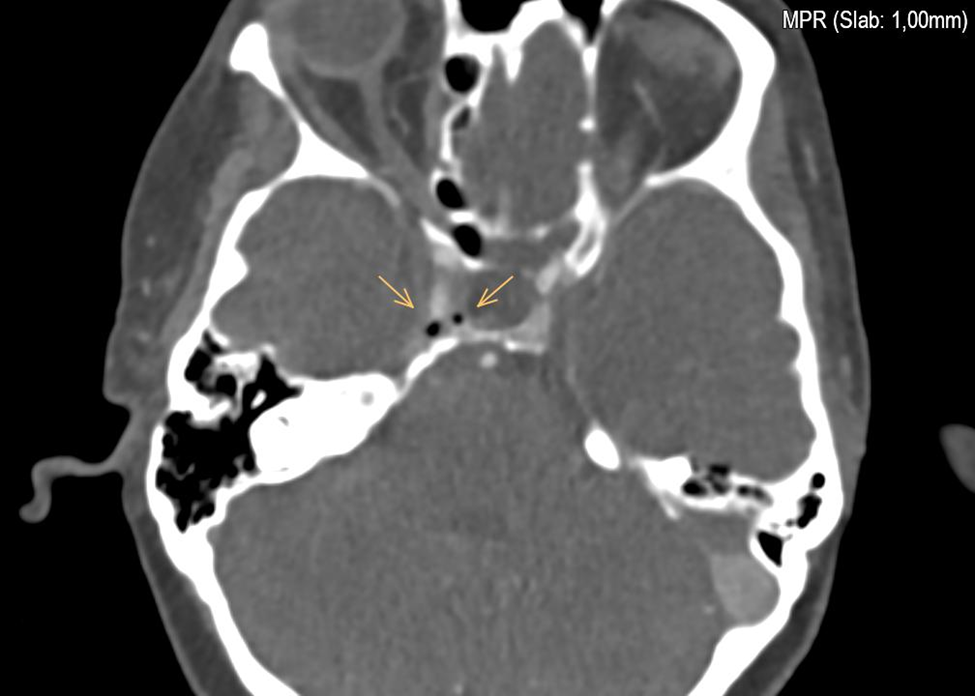

Neurovascular Assessment: An angiographic CT of the skull conducted during the neurological evaluation revealed the presence of air emboli in the cavernous sinus. Notably, echocardiographic assessment ruled out the presence of a patent foramen ovale (PFO), leaving the etiology of the air embolism due to several mechanisms unclear.

Primarily, they include a patent foramen ovale, the presence of right or left intrapulmonary shunts, and the forcing of air through the pulmonary filter. According to the literature on venous embolism, our case suggests that air likely migrated from the arm, passing through the right subclavian vein and entering the internal jugular vein on a cranial path. Once in the internal jugular vein, the air travels through the inferior petrosal sinus, ultimately reaching the cavernous sinus. Patients experiencing gas embolism may not exhibit symptoms; however, they can present with headache, nausea, vomiting, dizziness, or seizures. As the literature indicates, the etiology of these symptoms remains poorly understood.

Figure 2